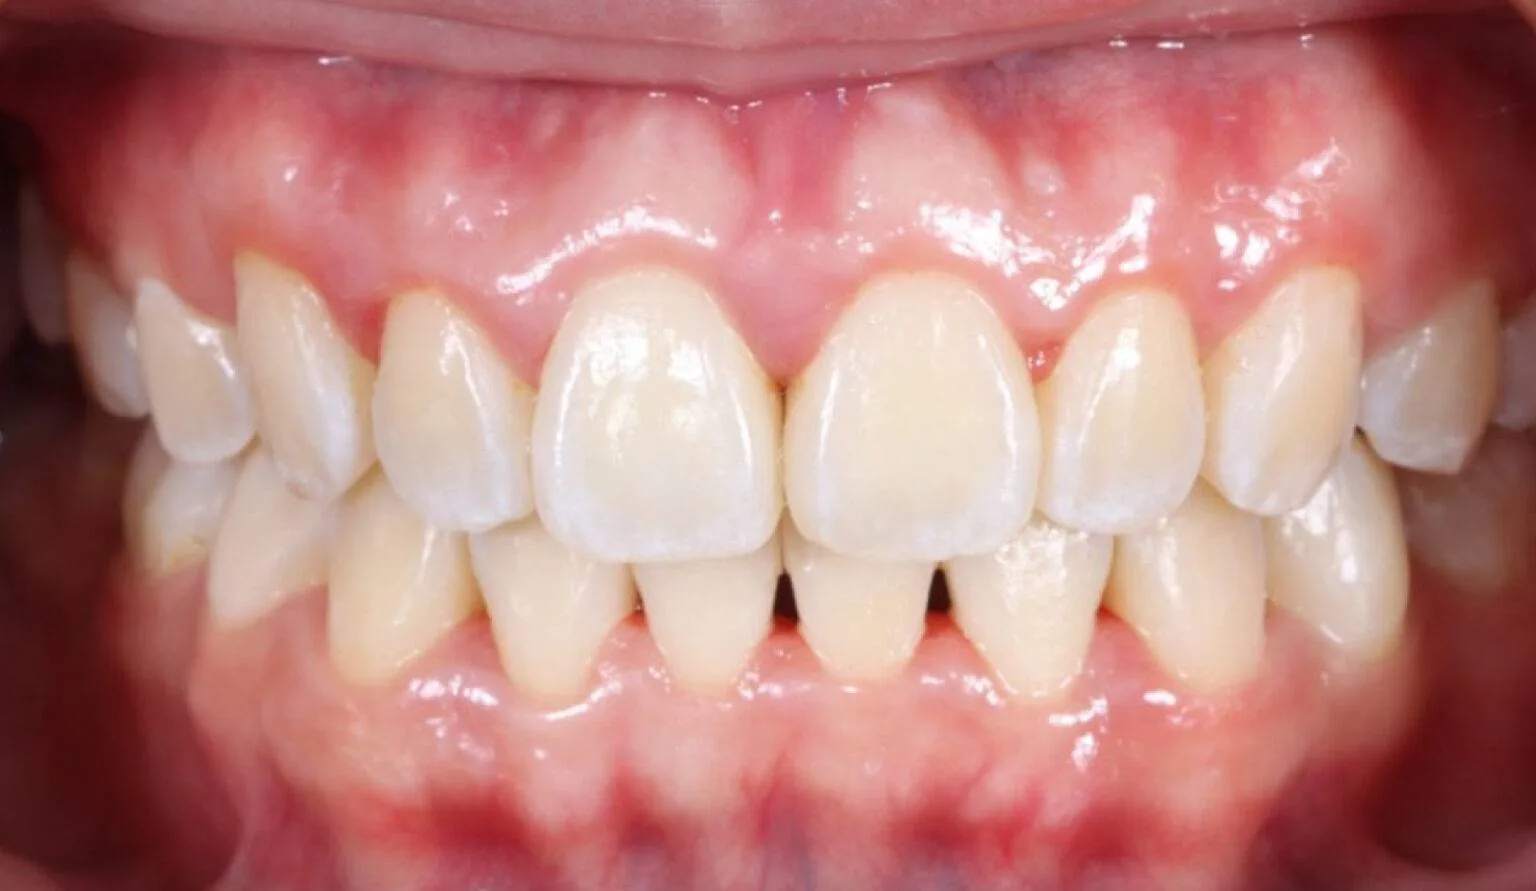

Before overcrowding treatment at SmileBox Clinic After overcrowding treatment at SmileBox Dental Clinic